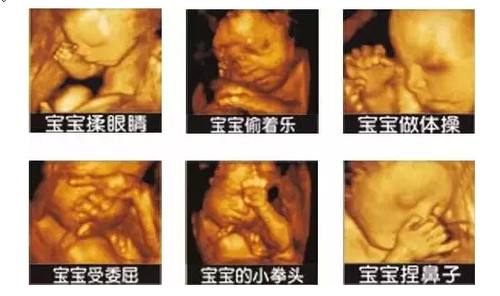

聊城怀孕做四维彩超的最佳时间?聊城博爱妇女儿童医院医师介绍说四维彩超是目前最先进的彩色超声设备,不仅可以拍摄极为细致的立体、连动的影像,而且能对胎儿早期、中期、晚期的发育状况进行评价,对胎儿的脑组织、肾脏、四肢等器官的生长情况进行观察,对胎儿的异常情况提供准确全面的科学依据。

过去孕妇进行产检基本都采用B超,但B超检查设备,只能检查胎儿的生理指标,四维彩超可以实时的观察人体内部器官的动态运动,它也能够多角度、多方位的观察宫内胎儿的生长发育情况,为早期诊断胎儿先天性体表畸形和先天性心脏疾病,像是唇裂、脊柱裂、 大脑等提供了准确的科学依据。

在孕28周左右:此阶段胎儿面部表情也比较丰富,皮下脂肪较以上饱满,胎儿各个部位较前期更加清晰,不仅对以上各类畸形的诊断更加明确,而且胎儿面部的各种表情,如吃手指、喝羊水、打呵欠、哭闹等表情清晰可见。特别是胎儿的某些畸形有可能在中孕晚期或孕晚期才表现出来,所以孕晚期的超声检查是必不可少的。